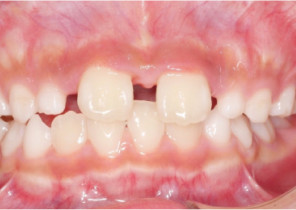

Étude de cas 2

7 ans et 11 mois, 24 étapes d’appareils® d’expansion palatine Invisalign.

Avec l’aimable autorisation du Dr David R. Boschken

Avant le traitement d’expansion avec les appareils d’expansion palatine Invisalign

Après le traitement d’expansion avec les appareils d’expansion palatine Invisalign